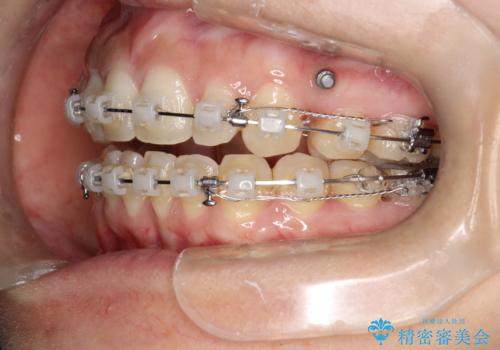

出っ歯で口が閉じずらい ワイヤーによる抜歯矯正

- 出っ歯で口が閉じずらくて、前歯でものかが噛み切れないとのことで来院されました。

上顎の前歯が前方に傾斜して、下顎の前歯と接触していない状態でした。

上顎の前から4番目の歯を両側抜歯して前歯を後方に移動させる計画としました。